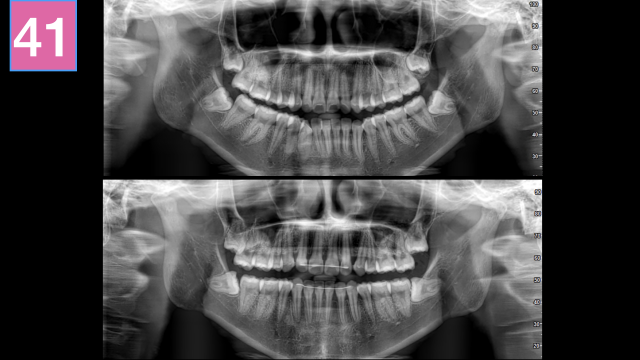

术前检查

术中治疗

术后总结